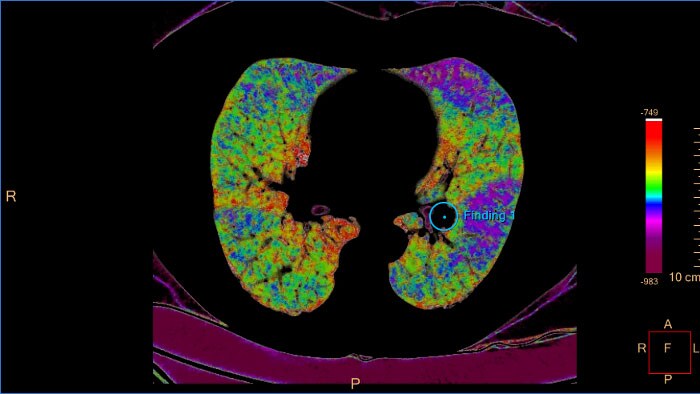

DPOC por TC

Suporta o controlo do processo destrutivo da doença pulmonar difusa (enfisema, asbestose, pulmão negro) e ajuda a localizar áreas específicas no pulmão afetado.